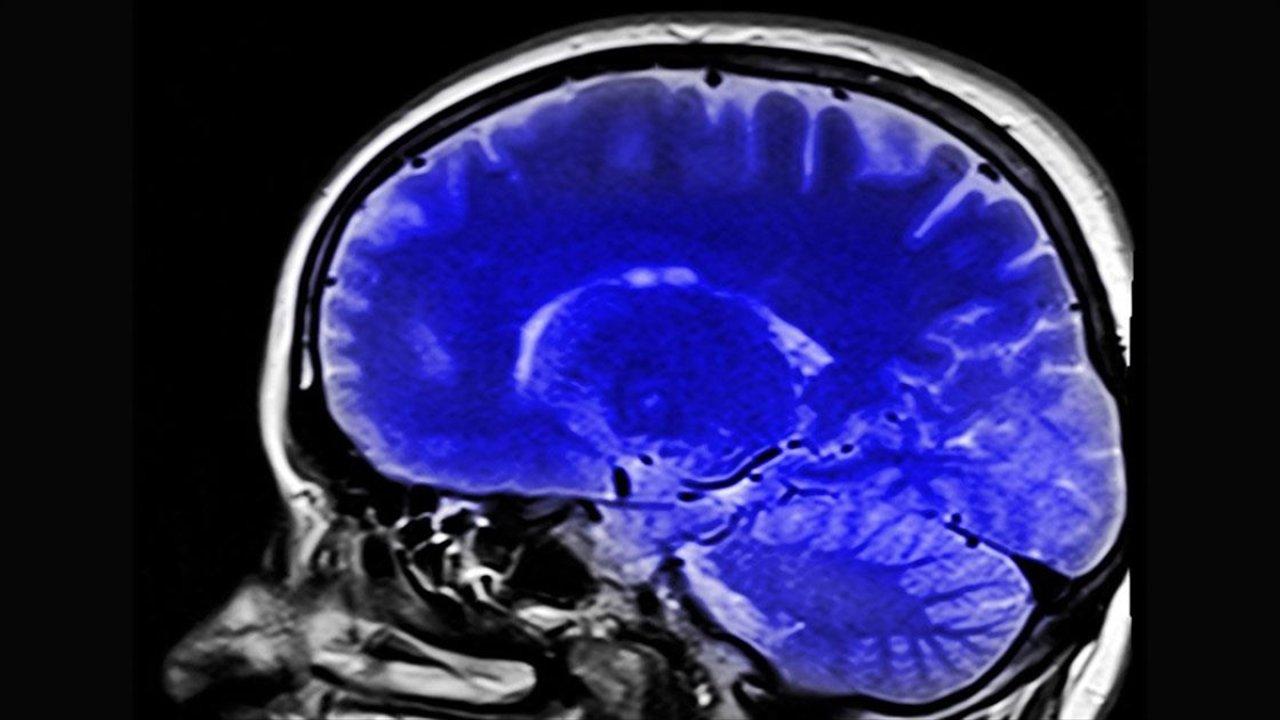

Kronik ağrılarınız son bulabilir! Beynin şifresi çözülüyor

ABD'de yapılan araştırma, ağrıların beyindeki kaynağına ilişkin yeni bulgular elde edilerek kronik ağrı çeken hastalara umut olunabileceğini ortaya koydu

AA - Nature Neuroscience dergisinde yayımlanan yeni araştırma kapsamında San Francisco şehrindeki California Üniversitesinden bilim insanları, yapay zeka algoritması kullanarak makine öğrenimi araçlarıyla topladıkları verileri analiz etti.

Bireylerin yaşadığı acıyı hafifletmek amacıyla potansiyel çözümlerin incelendiği araştırmada inme veya ampütasyon sonrası oluşan kronik ağrı bozukluklarının beyindeki yansımalarına dair bulgular elde edildi.

Araştırmacılar, katılımcıların kronik ağrı düzeylerine bağlı olarak tepkilerinin yansıdığı düşünülen beynin "anterior singulat korteks (ACC)" ve "orbitofrontal korteks (OFC)" adlı iki bölgesindeki aktivite değişikliklerine odaklandı.

Üçü inme sonrası, biri de kesilmiş olmasına rağmen sanki uzvu varmış gibi ağrı şikayeti bulunan katılımcılara ACC ve OFC'lerindeki aktivite değişikliklerini tespit etmeyi hedefleyen elektrotlar, cerrahi müdahaleyle yerleştirildi.

Katılımcılardan gün içinde birkaç kez yaşadıkları acıyı nasıl derecelendirdikleri, duygusal olarak nasıl hissettirdiği gibi soruları yanıtlamaları istendi, bu sırada hastaların ACC ve OFC'lerindeki aktivitenin anlık görüntüleri kaydedildi.

Beyin aktivitelerini ortaya çıkarmaya yönelik ilk çalışma

Araştırmacılar, elde ettikleri sonuçlarla kronik ağrının beyinde nasıl belirdiğine dair daha derin bir anlayış kazanarak beyin aktivitelerini modüle etmek amacıyla yenilikçi stratejiler geliştirmeyi ve bu acı verici durumdan şikayetçi olanlara ihtiyaç duydukları rahatlamayı sağlamayı umduklarını söyledi.

Bunun, "ağrı algısının altında yatan beyin aktivitelerini ortaya çıkarmaya yönelik ilk çalışma" olduğu bilgisini veren araştırmacılar, ağrının beyindeki kaynağının belirlenmesinin, kronik ağrıdan kaynaklanan acıyı hafifletmek için beyin aktivitesini değiştirebilen yeni terapilerin geliştirilmesini sağlayacağını kaydetti.

"Ağrı hakkında anlayamadığımız pek çok şey var"

ABD'nin California Üniversitesi Anestezi ve Nörolojik Cerrahi Bölümü'nden Doç. Dr. Prasad Shirvalkar, çalışmayla ilgili "Düşündüğümüzde ağrı, yaşadığımız en temel tecrübelerden biridir. Buna rağmen halen ağrı hakkında anlayamadığımız pek çok şey var." açıklamasında bulundu.

Shirvalkar, akut ağrılar tecrübe edildiğinde MR taramalarıyla beynin ACC ve OFC bölgelerindeki yansımalarını görebildiklerini belirterek, buradan yola çıkarak beyindeki ACC ve OFC bölgelerinin kronik ağrı oluştuğunda nasıl tepki verecekleriyle ilgilendiklerini kaydetti.

Ağrının zamanla nasıl değişeceğini merak ettiklerini vurgulayan Shirvalkar, yüksek derecedeki kronik ağrı konusunda beynin ne tür işaretler vereceğine, beynin ağrıyı tahmin edip edemeyeceğine odaklandıklarını dile getirdi.